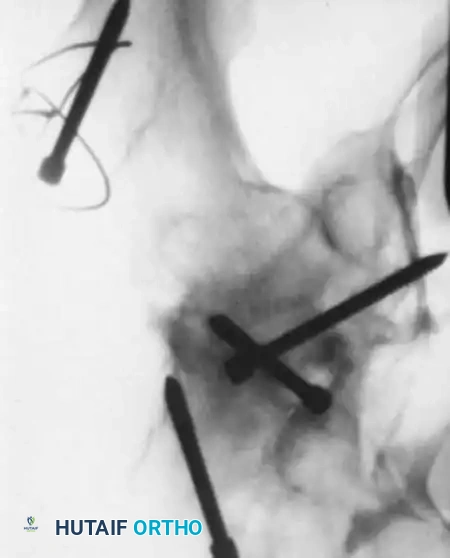

Fig. 9: Intraoperative fluoroscopy confirming pin placement across the physis.

- Reduction: Perform a gentle closed reduction using longitudinal traction, abduction, and internal rotation. Verify anatomic alignment on AP and lateral fluoroscopy.

- Capsular Decompression: If closed reduction is achieved, perform a percutaneous capsular aspiration or a limited (1-2 cm) arthrotomy to evacuate the hematoma.

- Use two or three partially threaded cannulated screws (typically 4.5 mm or 6.5 mm depending on the child's size).

- Crucial Step: The pediatric femoral neck is extremely hard. You must overdrill the near cortex to achieve a lag effect and prevent fracture distraction.

- Stop the threads short of the physis to prevent growth arrest. Do not use adult triflanged nails, as the impaction force will distract the fracture or separate the physis.